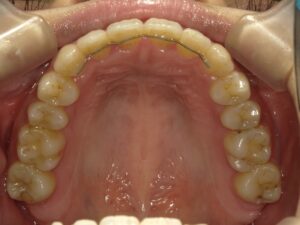

だいぶ歯が出てきたのがわかると思います。

この後下の歯並びを整えていき、噛み合わせが安定したら終了します。

治療終了後は歯の後戻りが起きる可能性があるため、歯の裏側を細いワイヤーで固定し

その上からマウスピースなどを使用してもらい一定期間経過観察をしていきます。